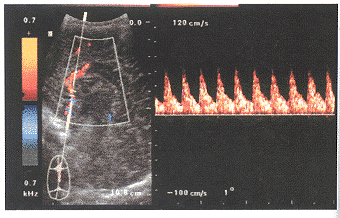

ACA的测定:从前囟探查,此时超声束与ACA夹角较小。可测得较准确的数据。在显示侧脑室矢状面,呈长眉状的无回声区,上面为胼胝体,其上方可见胼缘动脉、胼周动脉波动,下方为丘脑,前下方为尾状核,其前方可见大脑前动脉上升的情况。此时几乎可显示大脑前动脉及其部分分支的全貌。彩色血流显示红色,多普勒频谱为正向(图1、2)。

图1 ACA彩色血流

图2 ACA多普勒频谱